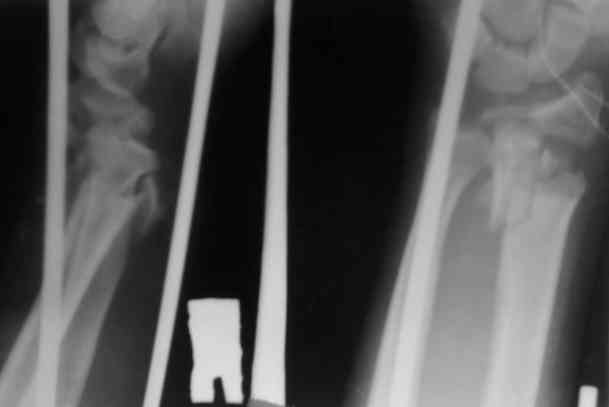

Уважаемые участники форума,поделитесь опытом...Поступил больной 23.03.07 в отделение нейрохирургии с диагнозом:кататравма, ушиб головного мозга ср.тяжести,линейный перелом лобной кости слева, открытые переломы костей обоих предплечий.

По дежурству перооперирован.На оба предплечья наложены ЧД аппараты (см. приложение)Через 3 дня переведен в травм.отделение. Мнения коллег о дальнейшей тактике разделились: накостно с трансплантацией или ЧДО аппаратом Илизарова, с целью добиться, хотя бы относительно удовлетворительного стояния.На сегоднешний день выраженный болевой синдром, больше слева.Раны на предплечье заживают первично.

Слева стояние вроде приемлемо,хотя снимки не очень информативны.

Очевилно, здесь аппаратный вариант далеко не исчерапал своих возможностей. Пока аппараты скомпонованы неоптимально - среднюю опору желательно было расположить не совсем рядом с проксимальной, а на 2-3 см выше перелома, закрепив на ней единственную спицу с упором, которая позволила бы управлять положением центрального

отломка лучевой кости.

По левому предплечью - суставной конец лучевой кости выглядит неплохо, больших ступенек не видно, так что можно попытаться 2-3 спицами с упорами встречно фиксировать эпиматефиз лучвой кости, установить на этом уровне кольцо, ссбросить перерастяжение и вскоре освободить кисть. В локтевую провести 2 спиц с упорами (сразу дистальнее перелома с упором от межкостного промежутка, в головку - встречно, закрепить на консольных приставкх на ту опору, которая сейчас средняя.

С правым дело хуже, хотя и в этом случае суставная площадка сохраняет форму, что оставляет шанс на закрытое ведение. Здесь как раз бы переввести спицу в луч проксимальнее перелома (скользнув ею по тылу локтевой кости). Установить на этом уровне кольцо. Закрепить и натянуть эту спицу в полукольце большего диаметра. За это полукольцо руками (или временно соединив его стержнями перпенидкулярно оси предплечья) центральный отломок сместить к тылу до восстановления оси.

Потом аккуратно сбросить перерастяжение за кисть, и посмотреть, что получится. Если суставная площадка сохранит форму, луче-локтевые взаимоотношения будут приемлемые, можно также фиксировать 2 спицами эпифиз, и потом освободить кисть.

Вариант с открытой репозицией фиксацией пластинкой, лучше с угловой стабильностью, также возможен.